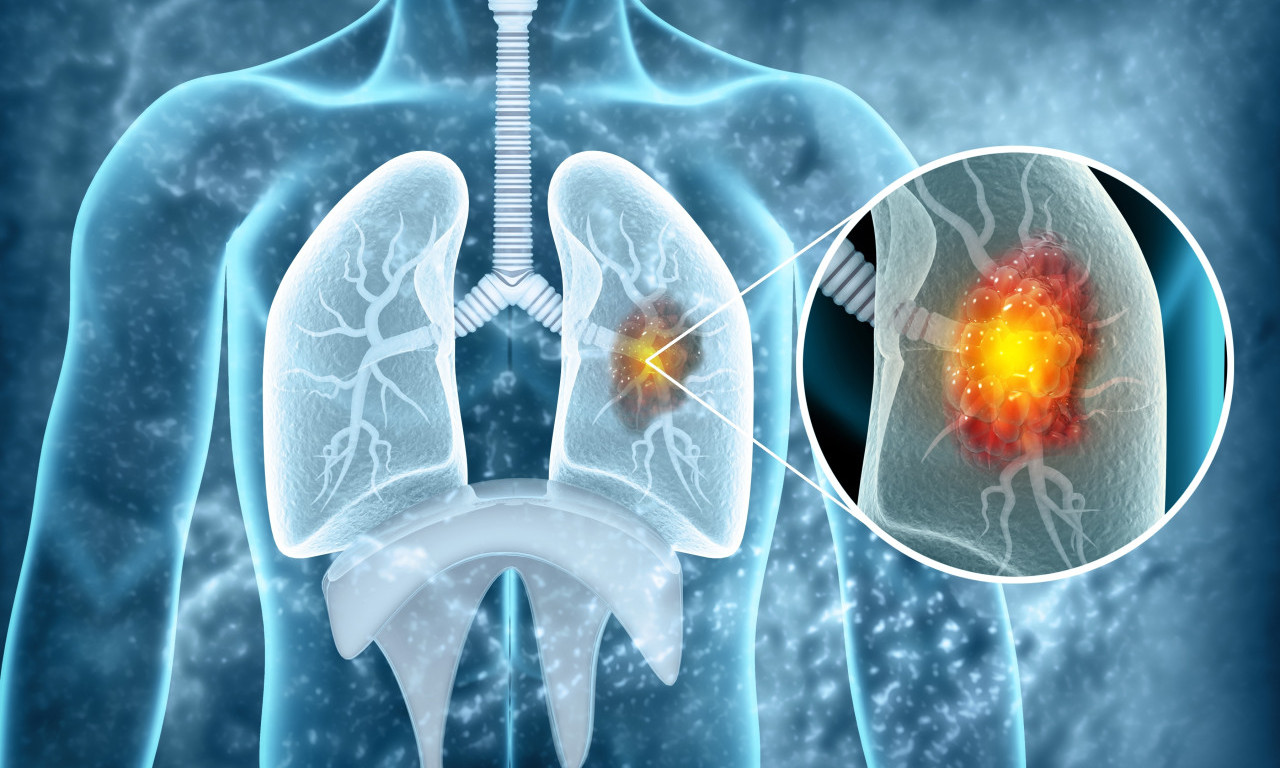

rak pluća

VEŠTAČKA INTELIGENCIJA OTKRIVA RAK PLUĆA MESEC DANA UNAPRED! Potrebno je uraditi osnovne medicinske analize

Da li je NOVI LEK rešenje globalnog problema? Lekari objavili da najefikasnije zaustavlja RAK PLUĆA

Rak pluća je vodeći uzrok smrti od raka u svetu, a godišnje ima 1,8 miliona smrtnih slučajeva od kancera pluća

CRNA STATISTIKA: 70% obolelih RAK PLUĆA otkrije tek kad su ŠANSE ZA IZLEČENJE MINIMALNE, ovo je NAJVEĆI PROBLEM

Doktor je objasnio koje metode lečenja postoje u Srbiji i na koji način se određuje da li će pacijent biti podvrgnut inovativnom lečenju

Pneumolog, dr Vesna Ćerima Krstić u emisiji "Uranak" na televiziji K1 objašnjava da u ranoj fazi karcinom pluća nema nikakve simptome